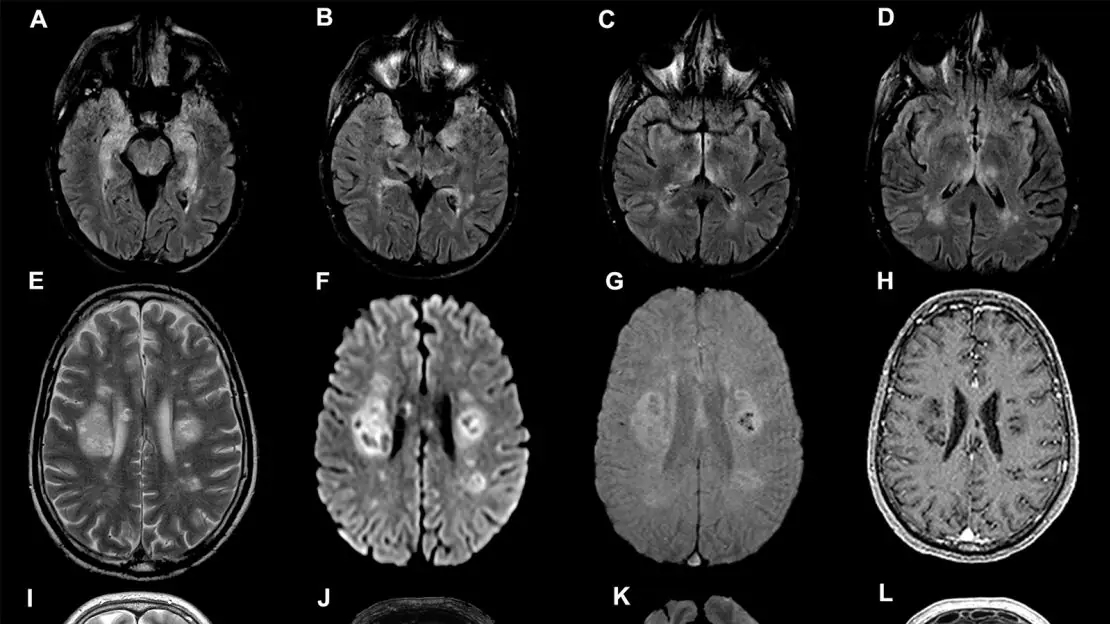

Brain tumors can affect people of any age and often develop silently. In the early stages, symptoms may be mild or mistaken for stress, fatigue, or common illnesses. However, recognizing warning signs early is critical, as timely diagnosis can significantly improve treatment outcomes. Below are key symptoms of a brain tumor that should never be ignored.

One of the most common warning signs is persistent headaches. These headaches may become more frequent or severe over time and are often worse in the morning or when lying down. Unlike typical headaches, they may not improve with usual pain medication.

Seizures can also be an early sign, especially in people who have never had them before. Seizures may range from full-body convulsions to brief episodes of confusion, muscle twitching, or loss of awareness.

Changes in vision are another important symptom. This may include blurred vision, double vision, loss of peripheral vision, or seeing flashes of light. Brain tumors can put pressure on the optic nerves or areas of the brain responsible for sight.

Cognitive and personality changes should not be overlooked. Difficulty concentrating, memory problems, confusion, or noticeable changes in behavior, mood, or personality may occur as a tumor interferes with brain function.

Some people experience nausea or vomiting, particularly in the morning. This can be caused by increased pressure inside the skull and is often not related to food intake or stomach illness.

Weakness, numbness, or loss of coordination may affect one side of the body. Trouble walking, frequent falls, or difficulty with balance and fine motor skills can signal a problem in areas of the brain that control movement.

Speech difficulties, such as slurred speech, trouble finding words, or difficulty understanding language, may also occur depending on the tumor’s location.